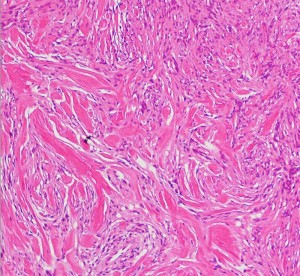

fibrous meningioma 線維性髄膜腫

spindle cellの増殖からなるfibrous meningiomaです。神経鞘腫 schwannomaとの違いは,nuclear palisadingが見られないことです。collagen fiberに富む部分(右側)

transitional typeとの混在で,meningothelial cell nest(右側)も混在します。一部にnuclear atypiaも見られますが,atypical meningiomaの診断には至りません。